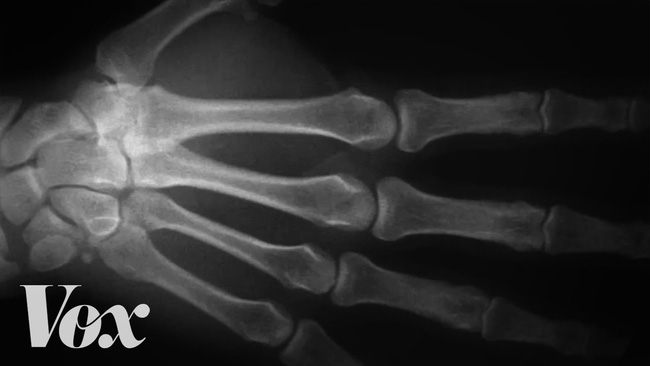

Điều gì thực sự xảy ra khi bạn bẻ ngón tay

Chắc chắn những tiếng "rắc rắc", "khục khục"... là âm thanh mà bạn nghe thấy sau mỗi lần bẻ khớp.

Nguyên nhân được các nhà khoa học đưa ra nhằm lý giải cho âm thanh này liên quan đến lỗ trống giữa 2 khớp xương.

Khi bẻ khớp, các mô liên kết trong ngón tay, chân tăng khối lượng, làm giảm áp lực trong khớp, dịch khớp dần biến thành những bong bóng trong lỗ trống.

Một khoảng đen xuất hiện khi bạn bẻ ngón tay

Cho đến khi áp lực xuống thấp nhất, các bong bóng này sẽ vỡ và phát ra âm thanh "khục khục" hay "rắc rắc".